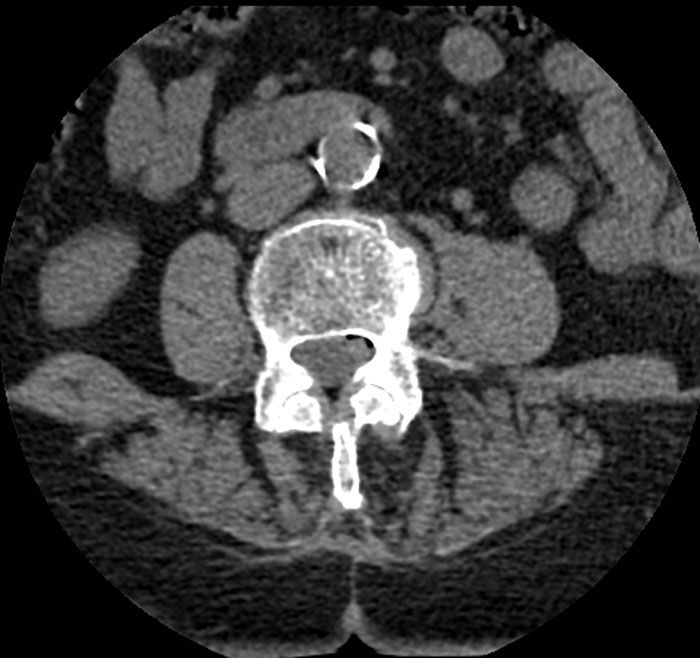

Performing an autopsy on an elderly patient with cardiac valve disease and found a 3 cm white plastic disc lodged in the ostium of one of the renal arteries. It was identical to the disc of the patient's tilting valve type mechanical aortic valve which was in place, intact, and functioning normally. We had no explanation for why an extra valve disc was present far downstream from the heart.

An in depth review of the patient's surgical history revealed that many years prior, during the installation of the patient's aortic valve, the cage for the valve broke while being installed and the disc had flown into the aorta and couldn't be retrieved. The surgeon immediately removed the broken cage, replaced the entire apparatus with another replacement valve and completed the surgery. We found no evidence that there was any subsequent investigation to determine the whereabouts of the lost valve component.

So for years (apparently unknown to most of his caretakers and even potentially to the patient) the patient had a cardiac valve disc lodged in his renal artery ostium, in such a way that it was non-obstructing and stable, and it was discovered as an incidental finding at the patient's autopsy.

Image credits: vonGekko